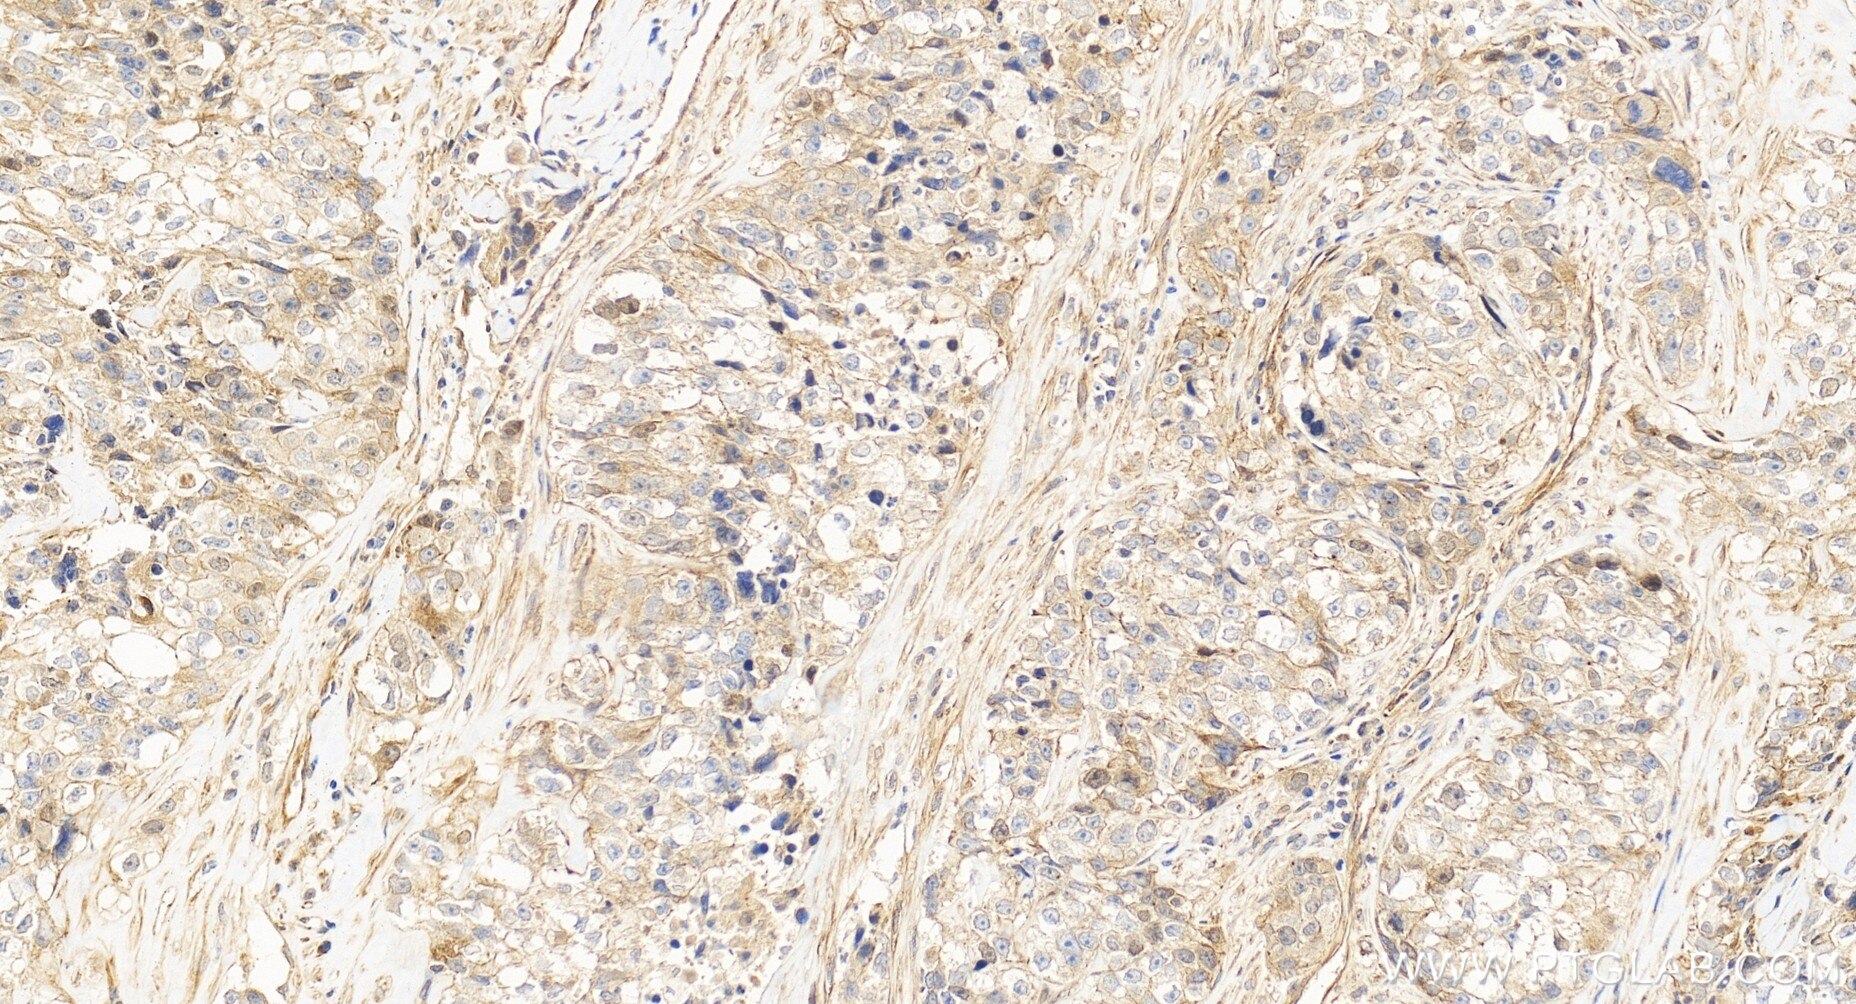

| Positive IHC detected in | human ovary cancer tissue Note: suggested antigen retrieval with TE buffer pH 9.0; (*) Alternatively, antigen retrieval may be performed with citrate buffer pH 6.0 |

| Immunohistochemistry (IHC) | IHC : 1:50-1:500 |

CUE domain-containing 2 (CUEDC2) is a ubiquitin-binding motif-containing protein involved in the regulation of the cell cycle, inflammation, and tumorigenesis. It is ubiquitously expressed in human tissues and organs, not only highly expressed in the normal brain, heart and testis, but also some kinds of cancers, such as breast, ovarian and kidney cancers. CUEDC2 could act as an adaptor protein to target IκB kinase (IKK) for dephosphorylation and inactivation by recruiting protein phosphatase (PP1), and thus repressed activation of the transcription factor NF-κB. Moreover, CUEDC2, is a key factor in endocrine resistance in breast cancer.